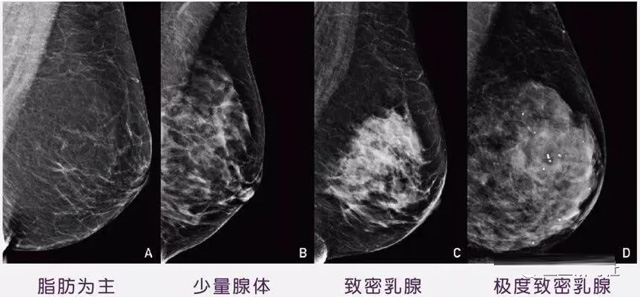

女性乳腺的自我檢查,特別是注意有小結節,腫塊,乳頭有液體滲出情況,需要通過乳腺DR,X光線,磁共振等影像技術檢查。胸的大小跟乳腺癌沒多大關系,乳腺的密度大發病率高一些,胸小脂肪少致密性大。更容易乳腺癌。這個還不能通過自我檢查來確認。致密乳腺組織看上去是白色或淺灰色需要通過乳腺X射線檢查。

乳腺X射線有輻射,40歲以下的女性沒有高危因素跟臨床特征,醫生都是不建議使用鉬靶檢查。乳腺超聲無創無輻射,對乳腺組織分辨率高。可以將乳腺腫塊從致密型乳腺組織中輕松查出來,多普勒模式檢查乳腺及病變,超聲小于1厘米的病灶非腫塊性乳腺癌檢出率低。超聲檢查結果依賴醫生水平和經驗,乳腺DR超聲推動乳腺超聲圖像的標準化,提高檢查的準確率。對乳腺組織內的細小鈣化灶, 從范圍、乳腺X射線形態以及分布特點上進行定性診斷。造影劑增強型乳腺X線攝影靜脈注射碘化造影劑結合乳房X線攝影。磁共振MRI對乳腺癌研究的深入對軟組織具有較高的分辨率等特點,在臨床上被廣泛認可。乳腺CT的探測器圍繞著乳房成像,無痛無擠壓,3D乳房圖像乳腺病灶的大小、數量、形狀、位置以及血管分布。一次掃描可創建多達兩千張投影圖像 。乳腺PET,適合普通人群和乳腺癌高危人群早期檢測,發現極早期微小病灶并明確定性。